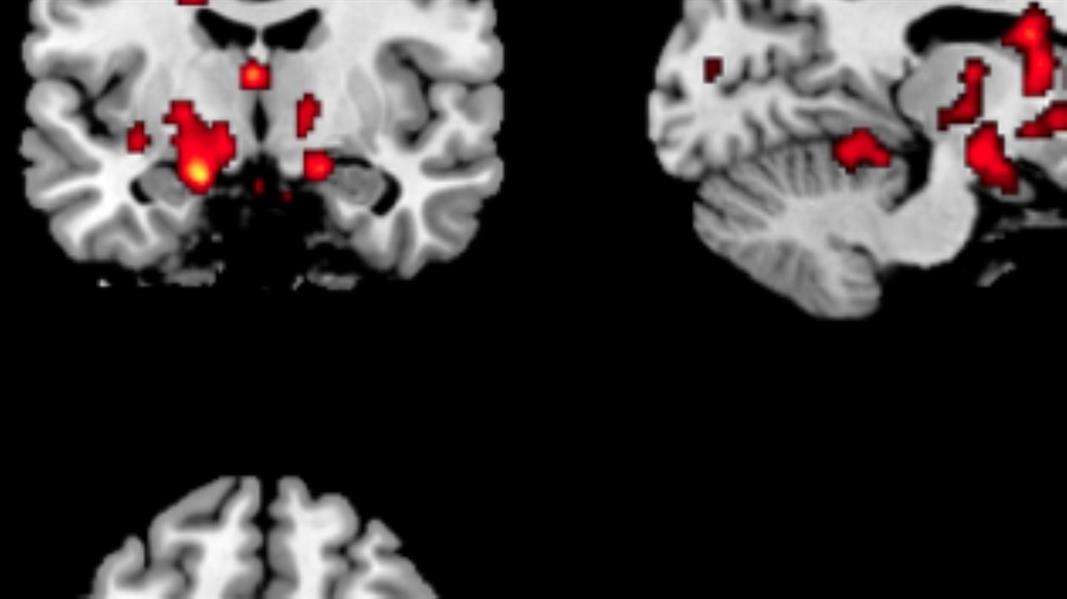

لم يتم الكشف عن المتلازمة إلا في بدايات عام 2000، وقد اعتبر الطب والمجتمع المصابين بها أشخاصاً خارقين، وتم رصد من 30- 60 شخصا مصابا فقط حول العالم، حيث أفادت الدراسات بأن المنطقة الدماغية التي تساعد في عملية التذكر تكون أكبر في دماغ المصابين.

وجرى تشخيص أول حالة إصابة عام 2006، لفتاة عمرها 14 عاماً من قبل فريق متخصص في جامعة كاليفورنيا ، كما تم تشخيص نحو 25 حالة حتى عام 2013 بعد إجراء التصوير بالرنين المغناطيسي على الأشخاص المصابين وتم اكتشاف أن المسؤولة عن حفظ الذكريات عندهم أكبر 7 مرات مقارنةً بغير المصابين.